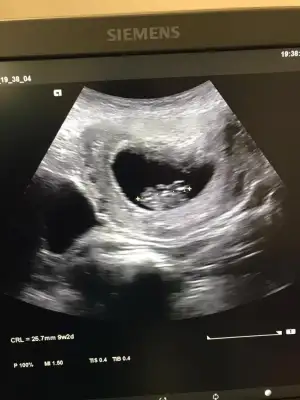

Evet karindan bakildi. O zaman.4+6 olan usg var gerisi hiç belli degil onlarda küçük usg dedimkarındanmı bakıldı 4+6 hafta usg

Kaç haftalık 6 7 olmalı erkek keseye göreKese konumundan bakabilir misiniz rica etsem

7 haftalık ay hadi inşallah teori doğru tutar iki kızım var teşekkür ederimKaç haftalık 6 7 olmalı erkek keseye göre